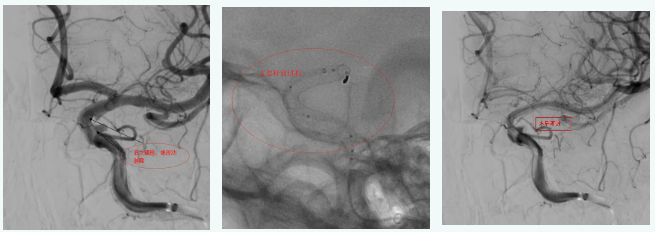

病例1

眼动脉动脉瘤合并后交通段动脉瘤,置入血流导向后,动脉瘤内即可形成造影剂滞留,手术过程30分钟,患者术后2天出院。